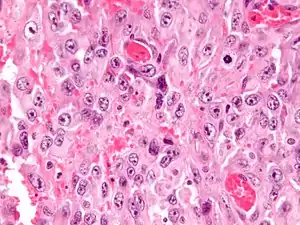

| Micrograph of an epithelioid sarcoma. H&E stain. | |

Histologically, epithelioid sarcoma forms nodules with central necrosis surrounded by bland, polygonal cells with eosinophilic cytoplasm and peripheral spindling.[3] Epithelioid sarcomas typically express vimentin, cytokeratins, epithelial membrane antigen, and CD34, whereas they are usually negative for S100, desmin, and FLI1 (FLI-1).[3] They typically stain positive for CA125.[4]

High mag.